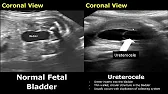

Fetal Bladder Ultrasound Normal Vs Abnormal Images | Genitourinary Tract Abnormalities USG

Dr. Sam’s Imaging Library15